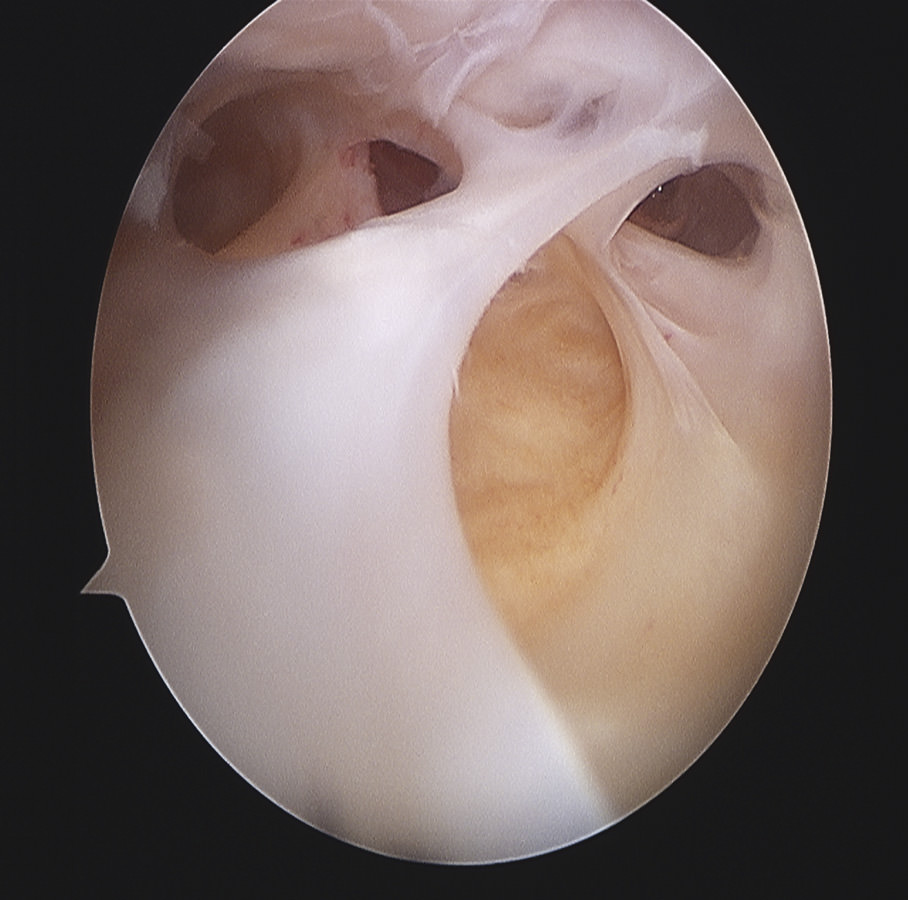

En los casos de rigideces precoces, el tratamiento incluye una rehabilitación agresiva con una analgesia adecuada y suficiente, con ayuda de férulas dinámicas y, si es preciso, antes de las primeras 8 semanas. Puede ser de ayuda una manipulación bajo anestesia cuando no se demuestran errores de malposicionamiento de la prótesis(5)(10); es discutible la práctica de una artroscopia pues existen autores que tienen buenos resultados con la artrolisis artroscópica con liberación del LCP(17)(18), mientras otros(19) refieren que solo una tercera parte mejoran a largo plazo. Sin embargo, los resultados son mejores, mejora la movilidad articular, con la artrolisis artroscópica(20)(21)(22)(23)(24)(25)(26)(27)(28) que con la manipulación bajo anestesia (Figura 4).

Siguiendo por los recesos lateral y medial (Figura 5) se llega a la zona suprapatelar, cuya fibrosis es la primera causa de limitación de la flexión (Figura 6). En este espacio hay que ser muy meticuloso para resecar con motor (Figura 7) y radiofrecuencia las adherencias, los nódulos, cíclopes (Figura 8), la fascia profunda del cuádriceps, con esqueletización de la cara anterior de fémur si es necesario, y liberar el alerón externo e interno, en función de la rótula: si está lateralizada (liberación solo lateral) o bien centrada (liberación lateral y medial), para facilitar el recorrido rotuliano. La limpieza de este espacio es fundamental para recuperar el máximo grado de flexión.

Figura 6. Bandas fibrosas articulares con disfunción patelofemoral y dolor anterior en prótesis de rodilla.